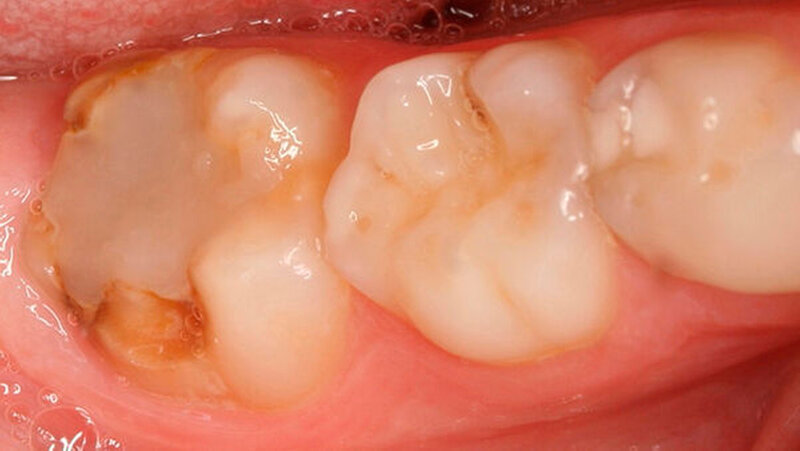

Bei einigen Patienten bestand allerdings auch schon im Milchgebiss eine Neigung zu Hypomineralisationen (Abbildung 3), klassifiziert wurden diese inzwischen als MDH (=deciduous molar hypomineralization) [Elfrink et al., 2012]. Inwiefern eine Hypomineralisation im Milchgebiss aber tatsächlich einen Indikator für eine MIH im bleibenden Gebiss darstellt, ist bisher nicht genauer zu beschreiben [Elfrink et al., 2012].